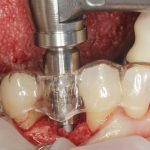

Inserti sonici in implantologia Premium

Le nuove tecnologie aiutano il clinico a migliorare i trattamenti da un punto di vista di

invasività e sicurezza. In questo case report viene mostrata la preparazione di un sito

implantare mediante inserti sonici dedicati